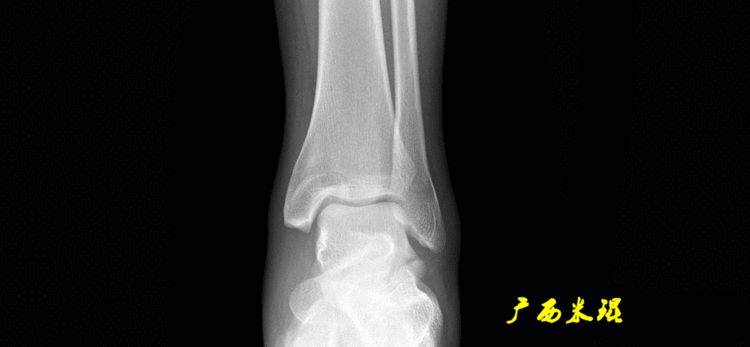

(3)踝关节中心踝关节中心点常用的也有3个,分别是骨骼(内、外踝表面间距)中点、踝关节间隙水平软组织中点和距骨宽度中点。

说明一下,膝关节线常常为膝关节间隙的水平线,也是膝关节的轴线,只有在比较正常的关节情况下使用,大多数情况下画出股骨远端机胫骨近端的关节线更好。(4)踝关节线踝关节线为胫骨远端软骨下骨之间的连线。

胫骨远端外侧角(mLDTA):胫骨远端切线(关节线)与下肢力线(机械轴)两者之间的外侧夹角,正常为89°±3°。

解剖胫骨远端外侧角(aLDTA):胫骨远端切线(关节线)与胫骨解剖轴两者之间的外侧夹角,正常为89°±3°。由于胫骨解剖轴与机械轴几乎一致,所以一般解剖胫骨远端内侧角与机械胫骨远端内侧角一致。

胫骨远端前倾角(ADTA):矢状面上胫骨远端的关节切线与胫骨解剖轴形成的夹角叫胫骨远端前倾角,正常为80°±2°。